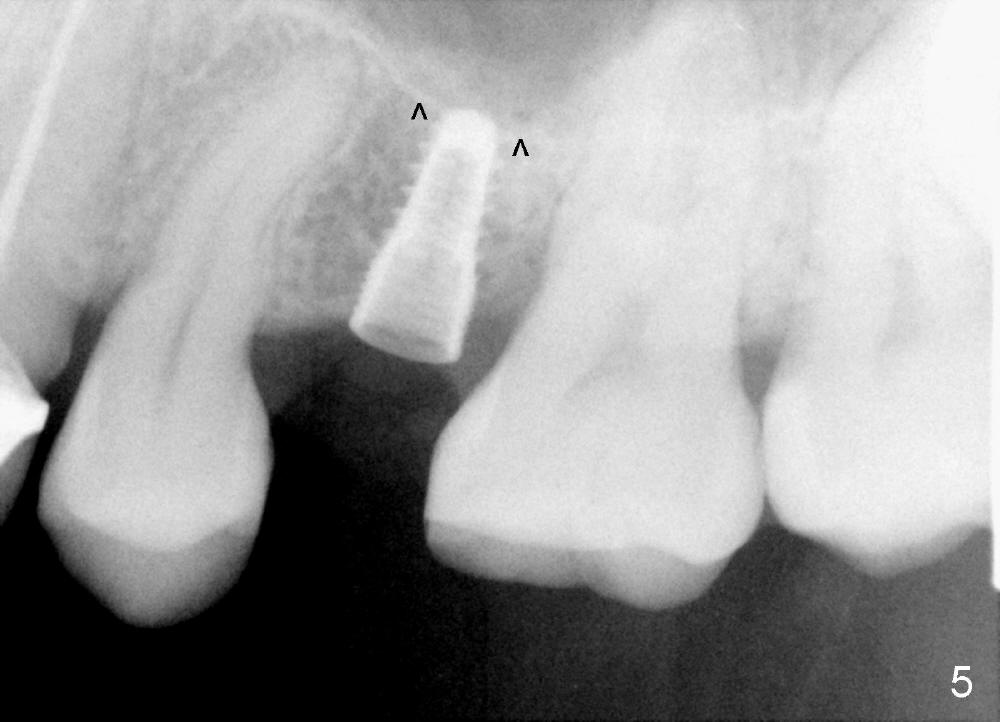

A 39-year-old lady is a dental phobic and finally agrees to restore long-termed missing upper left 2nd premolar (Fig.1). The adjoining teeth tilt toward the edentulous space. To place a 3.8x8 mm submerged implant (Fig.2, CBCT coronal section), enameloplasty is done (compare Fig.1 dashed lines with Fig.3 <). Since the density of the cancellous bone (<100 Hounsfield units (HU)) is much lower than that of the crest (300-400 HU) (Fig.2' <), osteotomy is initiated by 2 mm pilot drill (Fig.3 P) and finished by osteotomes (2 and 3 mm), bone expanders (2.6 mm (Fig.4) and 3.2 mm) and 3.8 mm tap drill. The implant is placed as planned with insertion torque around 35 Ncm (Fig.5). The implant is further lifted into the sinus by 1 mm without bone graft following the last X-ray. A healing abutment (4.1x3) is placed (Fig.6 <).